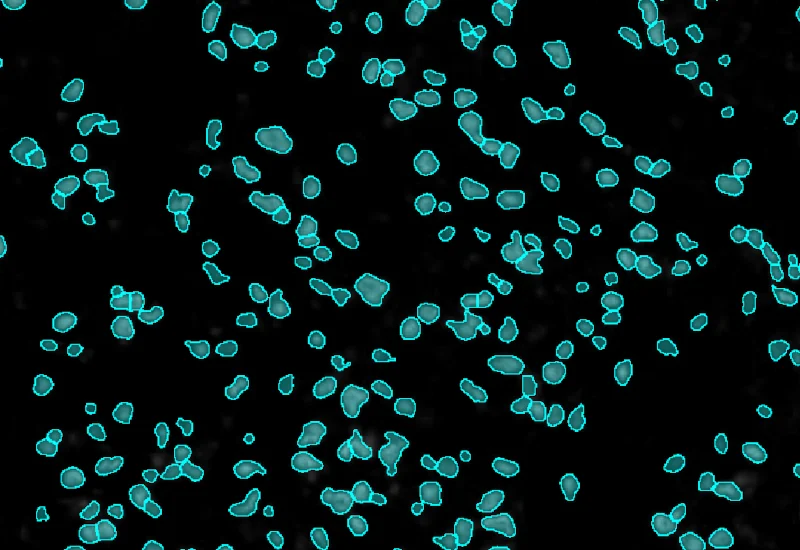

Detect nuclei and identify EBER-ISH–positive cells in EBV-stained tissue, and quantify total cell number, and number, density, and percentage of positive cells.

The EBER-ISH APP is specifically designed to analyse tissue samples stained by EBER-ISH probes. These probes vizualize the Epstein-Barr virus (EBV) EBER RNA. The EBER-ISH App first identifies nuclei and next detects EBER-ISH positive nuclei. The measurements provided by the APP are number of detected cells as well as the number, density and % of EBER-ISH positive cells.

Nuclei detection